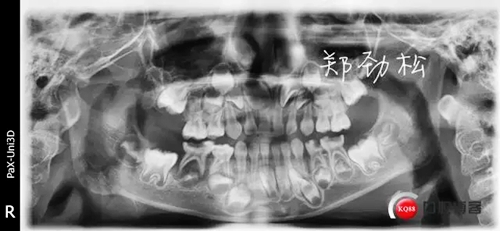

我的病例二 8E深齲導(dǎo)致的根尖炎

362433.jpg

常規(guī)的開(kāi)髓擴(kuò)根后vitapex糊劑充填,可見(jiàn)近中根有明顯的糊劑超充。